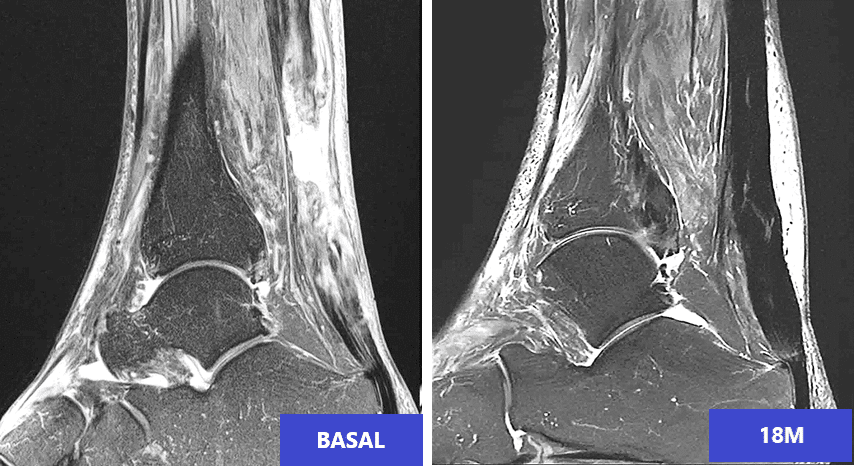

ITRT has just presented the results of a clinical trial with cultured mesenchymal stem cells that show, for the first time, that tendon can be regenerated.

The results indicate an unprecedented degree of regeneration of the tendon structure in 100% of patients, who resumed their practice of sports within 2 months.

The prestigious American Journal of Sports Medicine, has recently published the results and acknowledged them as “one of the most outstanding advances of recent decades”.